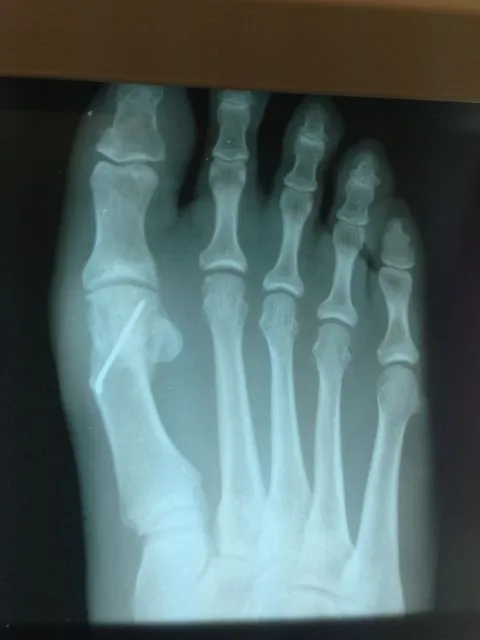

Before and immediately postop S/P bunionectomy

Pre and Postop Xrays

In the x-ray image below is a Hallux Valgus or what is more commonly known as a bunion deformity where the great toe is deviated towards the lesser toes causing abnormal structure which is a result of genetics, abnormal shoegear and abnormal mechanics will cause wearing of the joint and enlargement of the head of the long bone called the first metatarsal.

Post-surgical repair of the same patient bunion deformity with the great toe now in rectus (straight) position with surgically placed screws in the head of the first metatarsal that were used to secure fixation of the cut made across the bone to translate the head of the bone laterally in order to reduce the deformity. The screws will remain in place even after the bone heals.